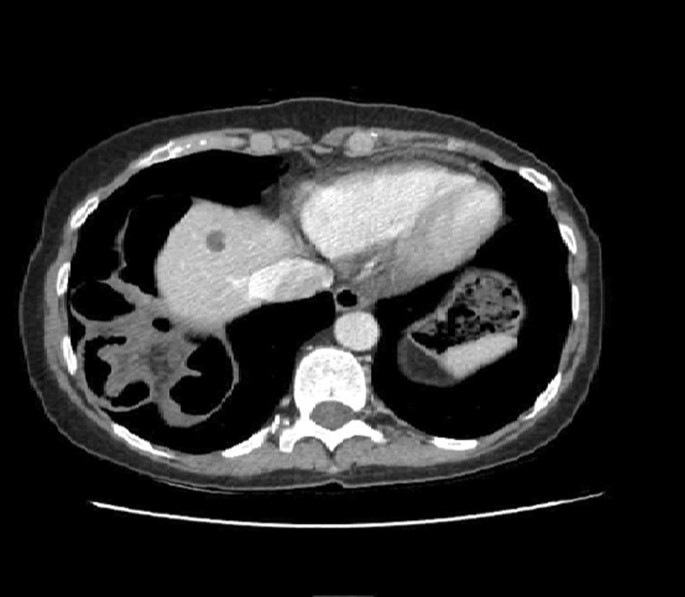

Chest X-ray revealed a right elevation of the diaphragm with the presence of small bowel into the right thoracic cavity (Fig. 1). Computerized tomography of the chest and abdomen was performed and confirmed the presence of loops of small intestine into the right hemithorax through the right diaphragm (Fig. 2).

In our case, the patient was hospitalized for vomiting and pain in the right upper abdomen and the right part of the thorax, which are the main symptoms depicted in literature for strangulating diaphragmatic hernia [6,7,8,9, 15]. Computerized tomography enabled us to evaluate the size, location, and type of diaphragmatic hernia. The elevation of the tension of the symptoms led without delay to a surgical intervention, which was lifesaving for the patient.